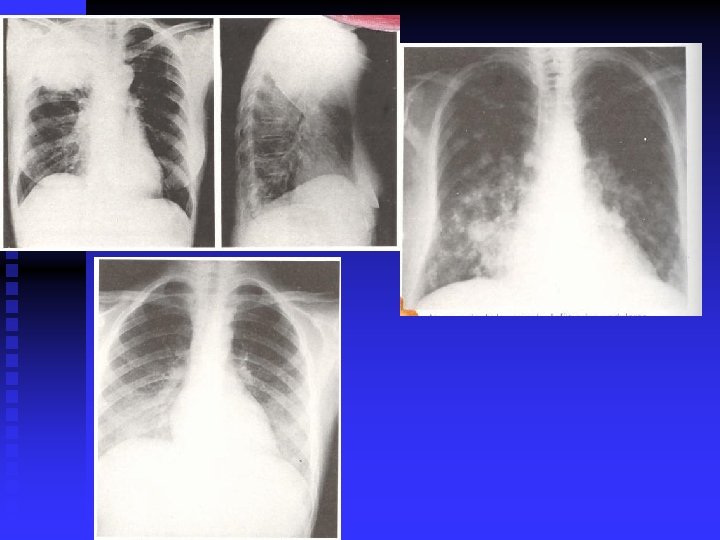

Clasificación Radiológica n Neumonía lobar, acinar o de los espacios aéreos n Neumonía de focos múltiples. Bronconeumonía n Neumonía intersticial n Neumonía necrotizante o cavitaria

Laboratorio y gabinete n n n n Radiografía del tórax. Indispensable para el diagnóstico. TAC (AR) útil para diagnosticar complicaciones y para el diagnóstico diferencial. Exámenes de esputo. Recomendables. Sangre: BH, QS, Hemocultivo. Pruebas serológicas. Líquido pleural: citoquímico, Gram, cultivo, etc. Técnicas invasivas: Broncoscopía (biopsia y cultivo) Punción traqueal y punción transtorácica

Neumonía Nosocomial Diagnóstico n Sospecha Clínica: Infiltrado alveolar nuevo con fiebre, esputo purulento o leucocitosis n n Radiología: Infiltrados alveolares y derrames Bacteriología: Cultivo de aspirado traqueal, sangre o líquido pleural. n Otros: ocasionalmente biopsia, broncoscopía.